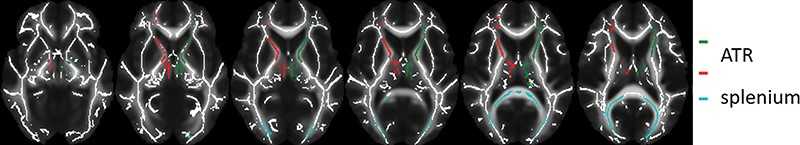

Patients received either MPH or a placebo for 16 weeks. Before and one week after treatment cessation, study participants underwent MRI, including diffusion tensor imaging (DTI). The outcome measure was change in fractional anisotropy (FA), which was assessed in three regions of interest (ROIs), as well as in a voxel-based analysis in brain white matter. Researchers analyzed data by using intention-to-treat linear mixed models for ROI analysis and a permutation-based method for voxel-based analysis with family-wise error correction.

In boys with ADHD, four months of treatment with MPH was associated with increased white matter FA. The effects were age dependent, as they were not observed in adults treated with MPH.

"The results show that ADHD medications can have different effects on the development of brain structure in children versus adults," Dr. Reneman said. "In adult men with ADHD, and both boys and adult men receiving placebo, changes in FA measures were not present, suggesting that the effects of methylphenidate on brain white matter are modulated by age."